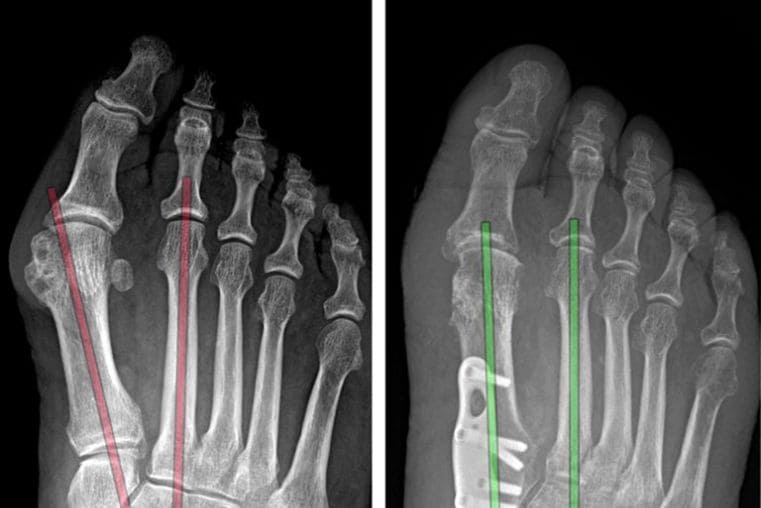

Um diagnóstico preciso, realizado por um especialista, é crucial para o sucesso do tratamento. A avaliação começa com um exame físico detalhado, analisando a marcha e os pontos de dor. Exames de imagem, como radiografias com carga, ultrassom e ressonância magnética, são fundamentais para avaliar as estruturas ósseas e os tecidos moles.

A cirurgia é indicada para casos de deformidades graves, instabilidade crônica ou fraturas complexas que não respondem ao tratamento inicial. Se você sofre com dores no pé ou tornozelo, agende uma avaliação com o Dr. Alessandro Leite para um diagnóstico correto e um plano de cuidado focado em você.